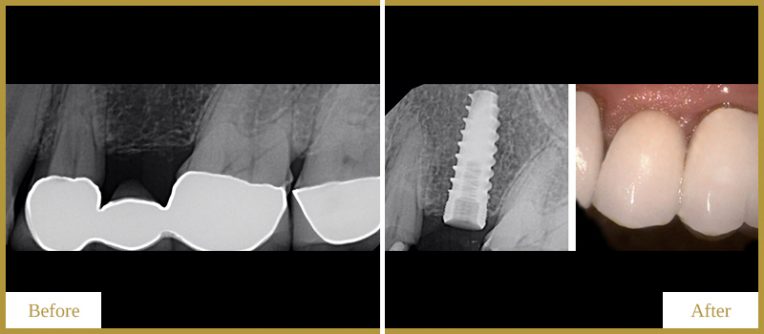

Smile Gallary

Amazing New Smile Make Overs

Dental Crowns

For a Beautiful Smile